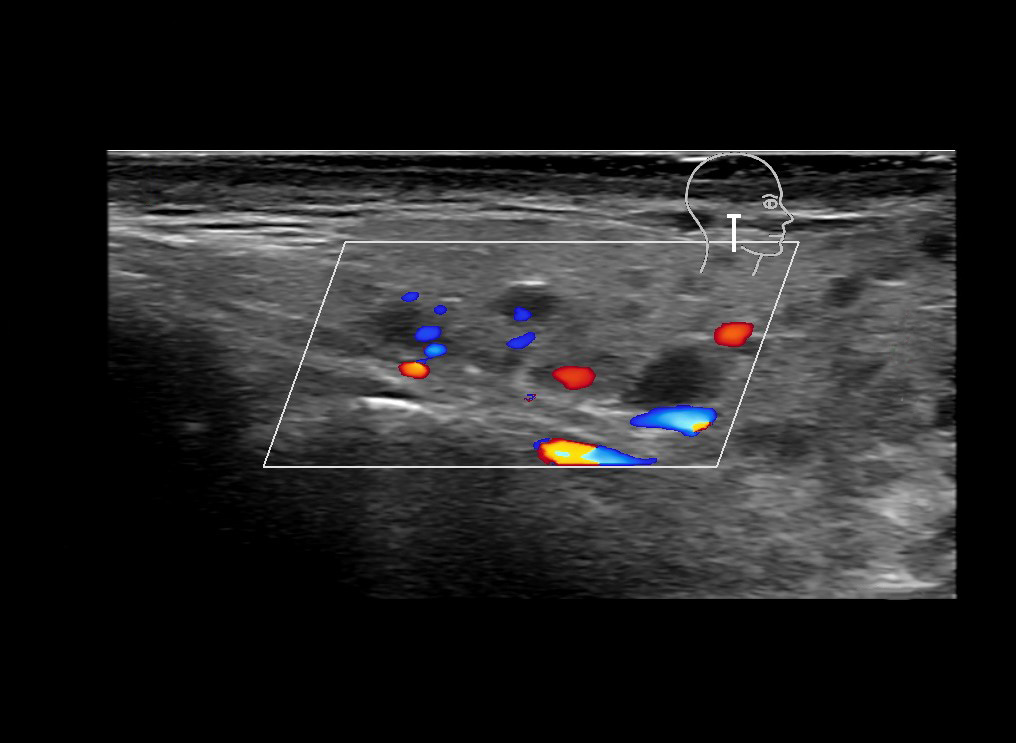

With ultrasound signs of inflammation can be visualized. Edema can be seen as a hyperechoic appearance of the subcutaneous fat, sometimes separated by hypoechoic fluid filled area’s, known as cobblestone appearance. Increased vascularization (hypervascularity) can be seen on colour Doppler. An abscess will appear as a fluid collection appearing as an irregular hypoechoic area with heterogeneous internal echoes and a thickened wall. Posterior acoustic enhancement can be present, and there is vascularity around but not within the mass. Under ultrasound guidance, abscesses can be managed by needle aspirations (18G)  under antibiotic cover.